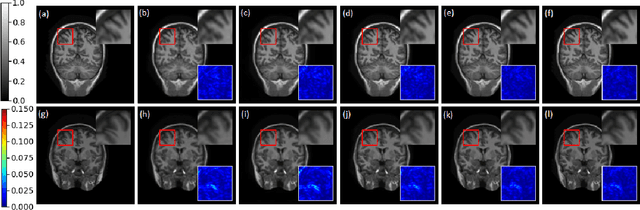

Abstract:Compressive sensing (CS) is widely used to reduce the image acquisition time of magnetic resonance imaging (MRI). Though CS based undersampling has numerous benefits, like high quality images with less motion artefacts, low storage requirement, etc., the reconstruction of the image from the CS-undersampled data is an ill-posed inverse problem which requires extensive computation and resources. In this paper, we propose a novel deep network that can process complex-valued input to perform high-quality reconstruction. Our model is based on generative adversarial network (GAN) that uses residual-in-residual dense blocks in a modified U-net generator with patch based discriminator. We introduce a wavelet based loss in the complex GAN model for better reconstruction quality. Extensive analyses on different datasets demonstrate that the proposed model significantly outperforms the existing CS reconstruction techniques in terms of peak signal-to-noise ratio and structural similarity index.

Abstract:Compressive sensing magnetic resonance imaging (CS-MRI) accelerates the acquisition of MR images by breaking the Nyquist sampling limit. In this work, a novel generative adversarial network (GAN) based framework for CS-MRI reconstruction is proposed. Leveraging a combination of patchGAN discriminator and structural similarity index based loss, our model focuses on preserving high frequency content as well as fine textural details in the reconstructed image. Dense and residual connections have been incorporated in a U-net based generator architecture to allow easier transfer of information as well as variable network length. We show that our algorithm outperforms state-of-the-art methods in terms of quality of reconstruction and robustness to noise. Also, the reconstruction time, which is of the order of milliseconds, makes it highly suitable for real-time clinical use.